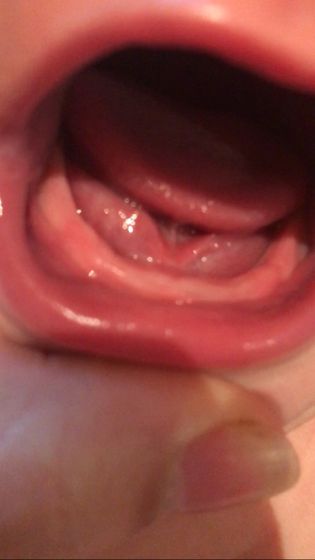

Вторую ночь плохо спим, капризничаем, носик течет, расстройство животика, вроде смотрю, но нечего похожее на зубики не вижу. Здесь же много опытных мамочек, подскажите пожалуйста что это может быть.

Скоро прорежутся судя по фото

У нас так же было, а потом оп и за одну ночь зуб вылез, тоже ничего не опухало)

Зубы нижние лезут, у дочки вообще ничего не опухало, просто вылезли я даже не заметила когда. Тоже лицо чесала сильно